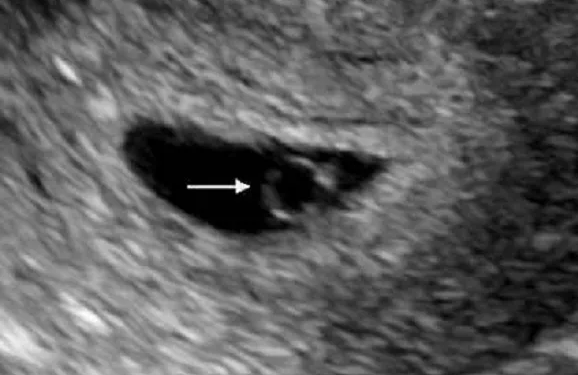

在婦科門診中,早期妊娠監(jiān)測是一項常見但充滿挑戰(zhàn)的工作。近期,一位女性患者在9月1日的超聲檢查中見到了卵黃囊,這本是一個令人欣喜的進展,然而在9月13日的復(fù)查中,卻仍未見到胎芽,最終被診斷為胚胎停育。這樣的情況在臨床中并不罕見,但對于經(jīng)歷者來說,無疑是一次沉重的打擊。本文將從這一病例出發(fā),探討早期妊娠的發(fā)展過程、胚胎停育的相關(guān)知識,以及面對這種情況時的心理調(diào)適與后續(xù)步驟。

卵黃囊是胚胎早期發(fā)育過程中的重要臨時器官,負(fù)責(zé)營養(yǎng)交換和血細(xì)胞生成,通常在孕5-6周出現(xiàn)。它的出現(xiàn)確認(rèn)了宮內(nèi)妊娠,排除了宮外孕的可能。在見到卵黃囊后,通常預(yù)期在一周內(nèi)可見胎芽和胎心搏動。

在文章開頭的病例中,從見到卵黃囊到12天后仍未見到胎芽,符合胚胎停育的診斷標(biāo)準(zhǔn)。